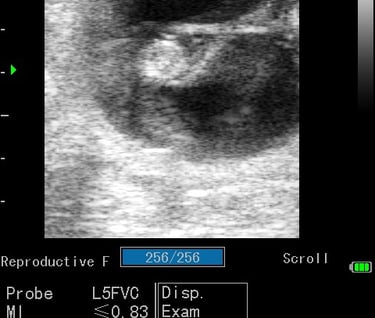

Gynécologie